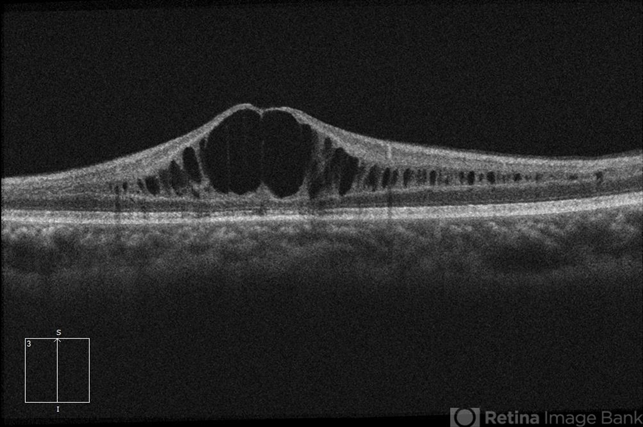

- 21-year-old male with congenital retinoschisis with bilateral macular involvement and large inner retinal hole OD . Foveoschisis reformed again OS, after it collapsed, compared to last visit in March 2016